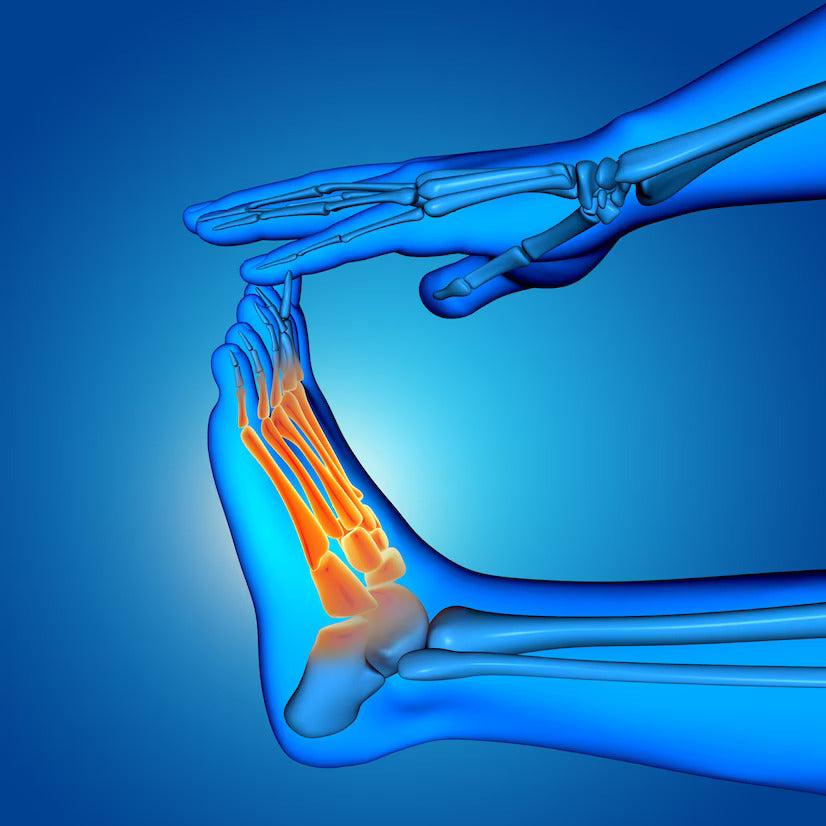

Tarsal Tunnel Syndrome is a condition that affects the foot and ankle area, causing pain, numbness, and tingling sensations. Similar to carpal tunnel syndrome in the wrist, Tarsal Tunnel Syndrome occurs when the tibial nerve, which runs along the inside of the ankle, becomes compressed or irritated. This condition can be quite painful and can significantly impact an individual's ability to walk and engage in daily activities.

Before delving into the symptoms of Tarsal Tunnel Syndrome, it is essential to have a basic understanding of the anatomy of the tarsal tunnel. The tarsal tunnel is a narrow passageway located on the inside of the ankle, along the inner side of the foot. It is covered by a thick ligament called the flexor retinaculum, which creates the roof of the tunnel. Within the tarsal tunnel, several structures pass, including nerves, blood vessels, and tendons. The most significant nerve passing through this tunnel is the tibial nerve, which is responsible for providing sensation and controlling the movement of the muscles in the foot and toes.

The symptoms of Tarsal Tunnel Syndrome can vary from person to person, depending on the severity and underlying causes. However, there are several common signs that individuals should be aware of. These symptoms typically occur along the path of the tibial nerve and may include:

- Pain: One of the primary symptoms of Tarsal Tunnel Syndrome is pain. This pain can manifest in different ways, such as a burning sensation, shooting pain, or a dull ache. It is often felt along the inside of the ankle, the bottom of the foot, or the arch area. The pain may worsen with prolonged standing or walking.

- Numbness and Tingling: Individuals with Tarsal Tunnel Syndrome may experience numbness or tingling sensations in the affected area. These sensations are commonly felt in the bottom of the foot or the toes. The numbness and tingling may come and go or persist for extended periods.

- Weakness: As Tarsal Tunnel Syndrome progresses, individuals may notice weakness in their foot or ankle. This weakness can make it difficult to perform activities that require strength or balance, such as walking or climbing stairs.

- Swelling: Some individuals with Tarsal Tunnel Syndrome may experience swelling around the ankle area. This swelling is often accompanied by discomfort and tenderness.

- Radiating Pain: In severe cases, the pain from Tarsal Tunnel Syndrome may radiate up the leg or down into the toes. This radiating pain can be sharp and intense and may make it challenging to pinpoint the exact location of the discomfort.